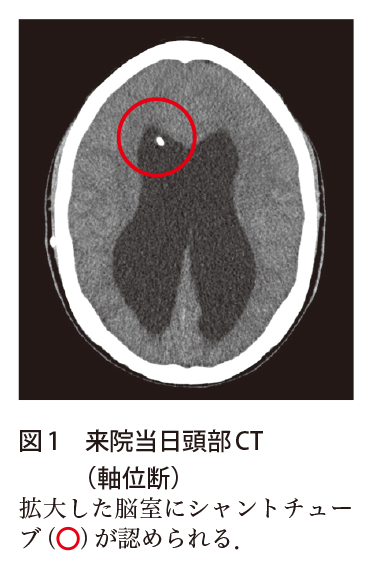

解答 解説 意識障害と腹部膨隆で救急搬送された10歳代男児 実践 画像診断q A 羊土社 レジデントノート 羊土社